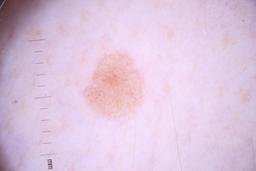

ISIC_4077341

- Challenge 2020: Training

Clinical

| Field | Value |

|---|---|

| acquisition_day | 1 |

| age_approx | 50 |

| anatom_site_1 | Trunk |

| anatom_site_2 | Anterior trunk |

| concomitant_biopsy | False |

| dermoscopic_type | contact non-polarized |

| diagnosis_1 | Benign |

| diagnosis_confirm_type | serial imaging showing no change |

| family_hx_mm | False |

| image_type | dermoscopic |

| lesion_id | IL_9238622 |

| patient_id | IP_1969685 |

| personal_hx_mm | True |

| sex | male |